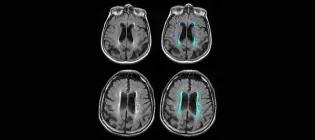

Over 1,200 staff and students collaborate across our core research areas, bringing together expertise that spans the body and life course. As part of driving progress in our core research areas, we host several leading research centres and house state-of-the-art technologies, which you can explore on this page. Want an introduction to our research first? Visit our Research page Explore the centres and units within our institute Anne Rowling Regenerative Neurology Clinic A globally leading, patient-centred, integrated care-research facility. The Clinic seamlessly integrates the best NHS health care with the best University health research, as key to discovering and trialling new treatments for neurological conditions. Euan MacDonald Centre for Motor Neuron Disease Research Pioneering vital research into motor neuron disease and unitiing over 300 scientists, doctors and healthcare professionals across Scotland, this centre is home to Europe’s largest clinical drugs trial for MND, MND-SMART. Jennifer Brown Research Laboratory A group working to improve understanding of what causes early labour, how we can develop treatments to prevent it and how we can better help newborn babies in those first crucial hours and days after birth. Muir Maxwell Epilepsy Centre A centre dedicated to investigating the causes of childhood-onset epilepsy. Simons Initiative for the Developing Brain Discovering the biological mechanisms underlying neurodevelopmental disorders - a research centre bringing together research groups across multiple sites. UKRI Mental Health Platform A network of researchers with the shared aim of accelerating research into severe mental illness and improving the diagnosis and treatment of those affected. British Heart Foundation Centre of Research Excellence A world-leading centre of excellence working to improve lives for people with cardiovascular, neurovascular, or metabolic health conditions. Edinburgh Clinical Research Facility State of the art facilities to support multidisciplinary clinical research locally, nationally and internationally. MRC/BHF Centre of Research Excellence in Advanced Cardiac Therapies (REACT) REACT unites academic, healthcare, industry and public partners to develop innovative DNA and RNA-based therapies capable of regenerating injured hearts and reversing established damage. It is co-led by King’s College London, the University of Edinburgh and the University of Oxford. Patrick Wild Centre A research centre that aims to better understand genetic conditions affecting brain development, and to improve the care and treatment available for people with these conditions. UK Dementia Research Institute at Edinburgh A centre of excellence that aims to elucidate the interactions within and between the brain vasculature, neurons, macroglia and microglia which control the trajectory of neurodegenerative disorders leading to dementia, and exploit this knowledge for therapeutic benefit. Centre for Pesticide Suicide Prevention A research and policy initiative working to reduce the number of pesticide suicides worldwide. Edinburgh Imaging World class imaging for research and diagnostic needs, working with academic researchers, NHS clinicians and commercial imaging organisations, including biotech, pharmaceutical & private medical industries. MS Society Edinburgh Centre for MS Research A multidisciplinary centre-without-walls funded by the MS Society, dedicated to laboratory, translational and clinical research into multiple sclerosis. Row Fogo Centre for Research into Ageing and the Brain Researchers working together to improve the understanding of how blood vessel diseases can damage the brain, leading to stroke, cognitive decline, dementia and mobility problems. UKRI Hub for Metabolic Psychiatry Part of the Mental Health Platform, this Hub brings together six interdisciplinary workstreams operating in concert to advance our understanding of the connection between metabolic and mental health. This article was published on 2026-03-17